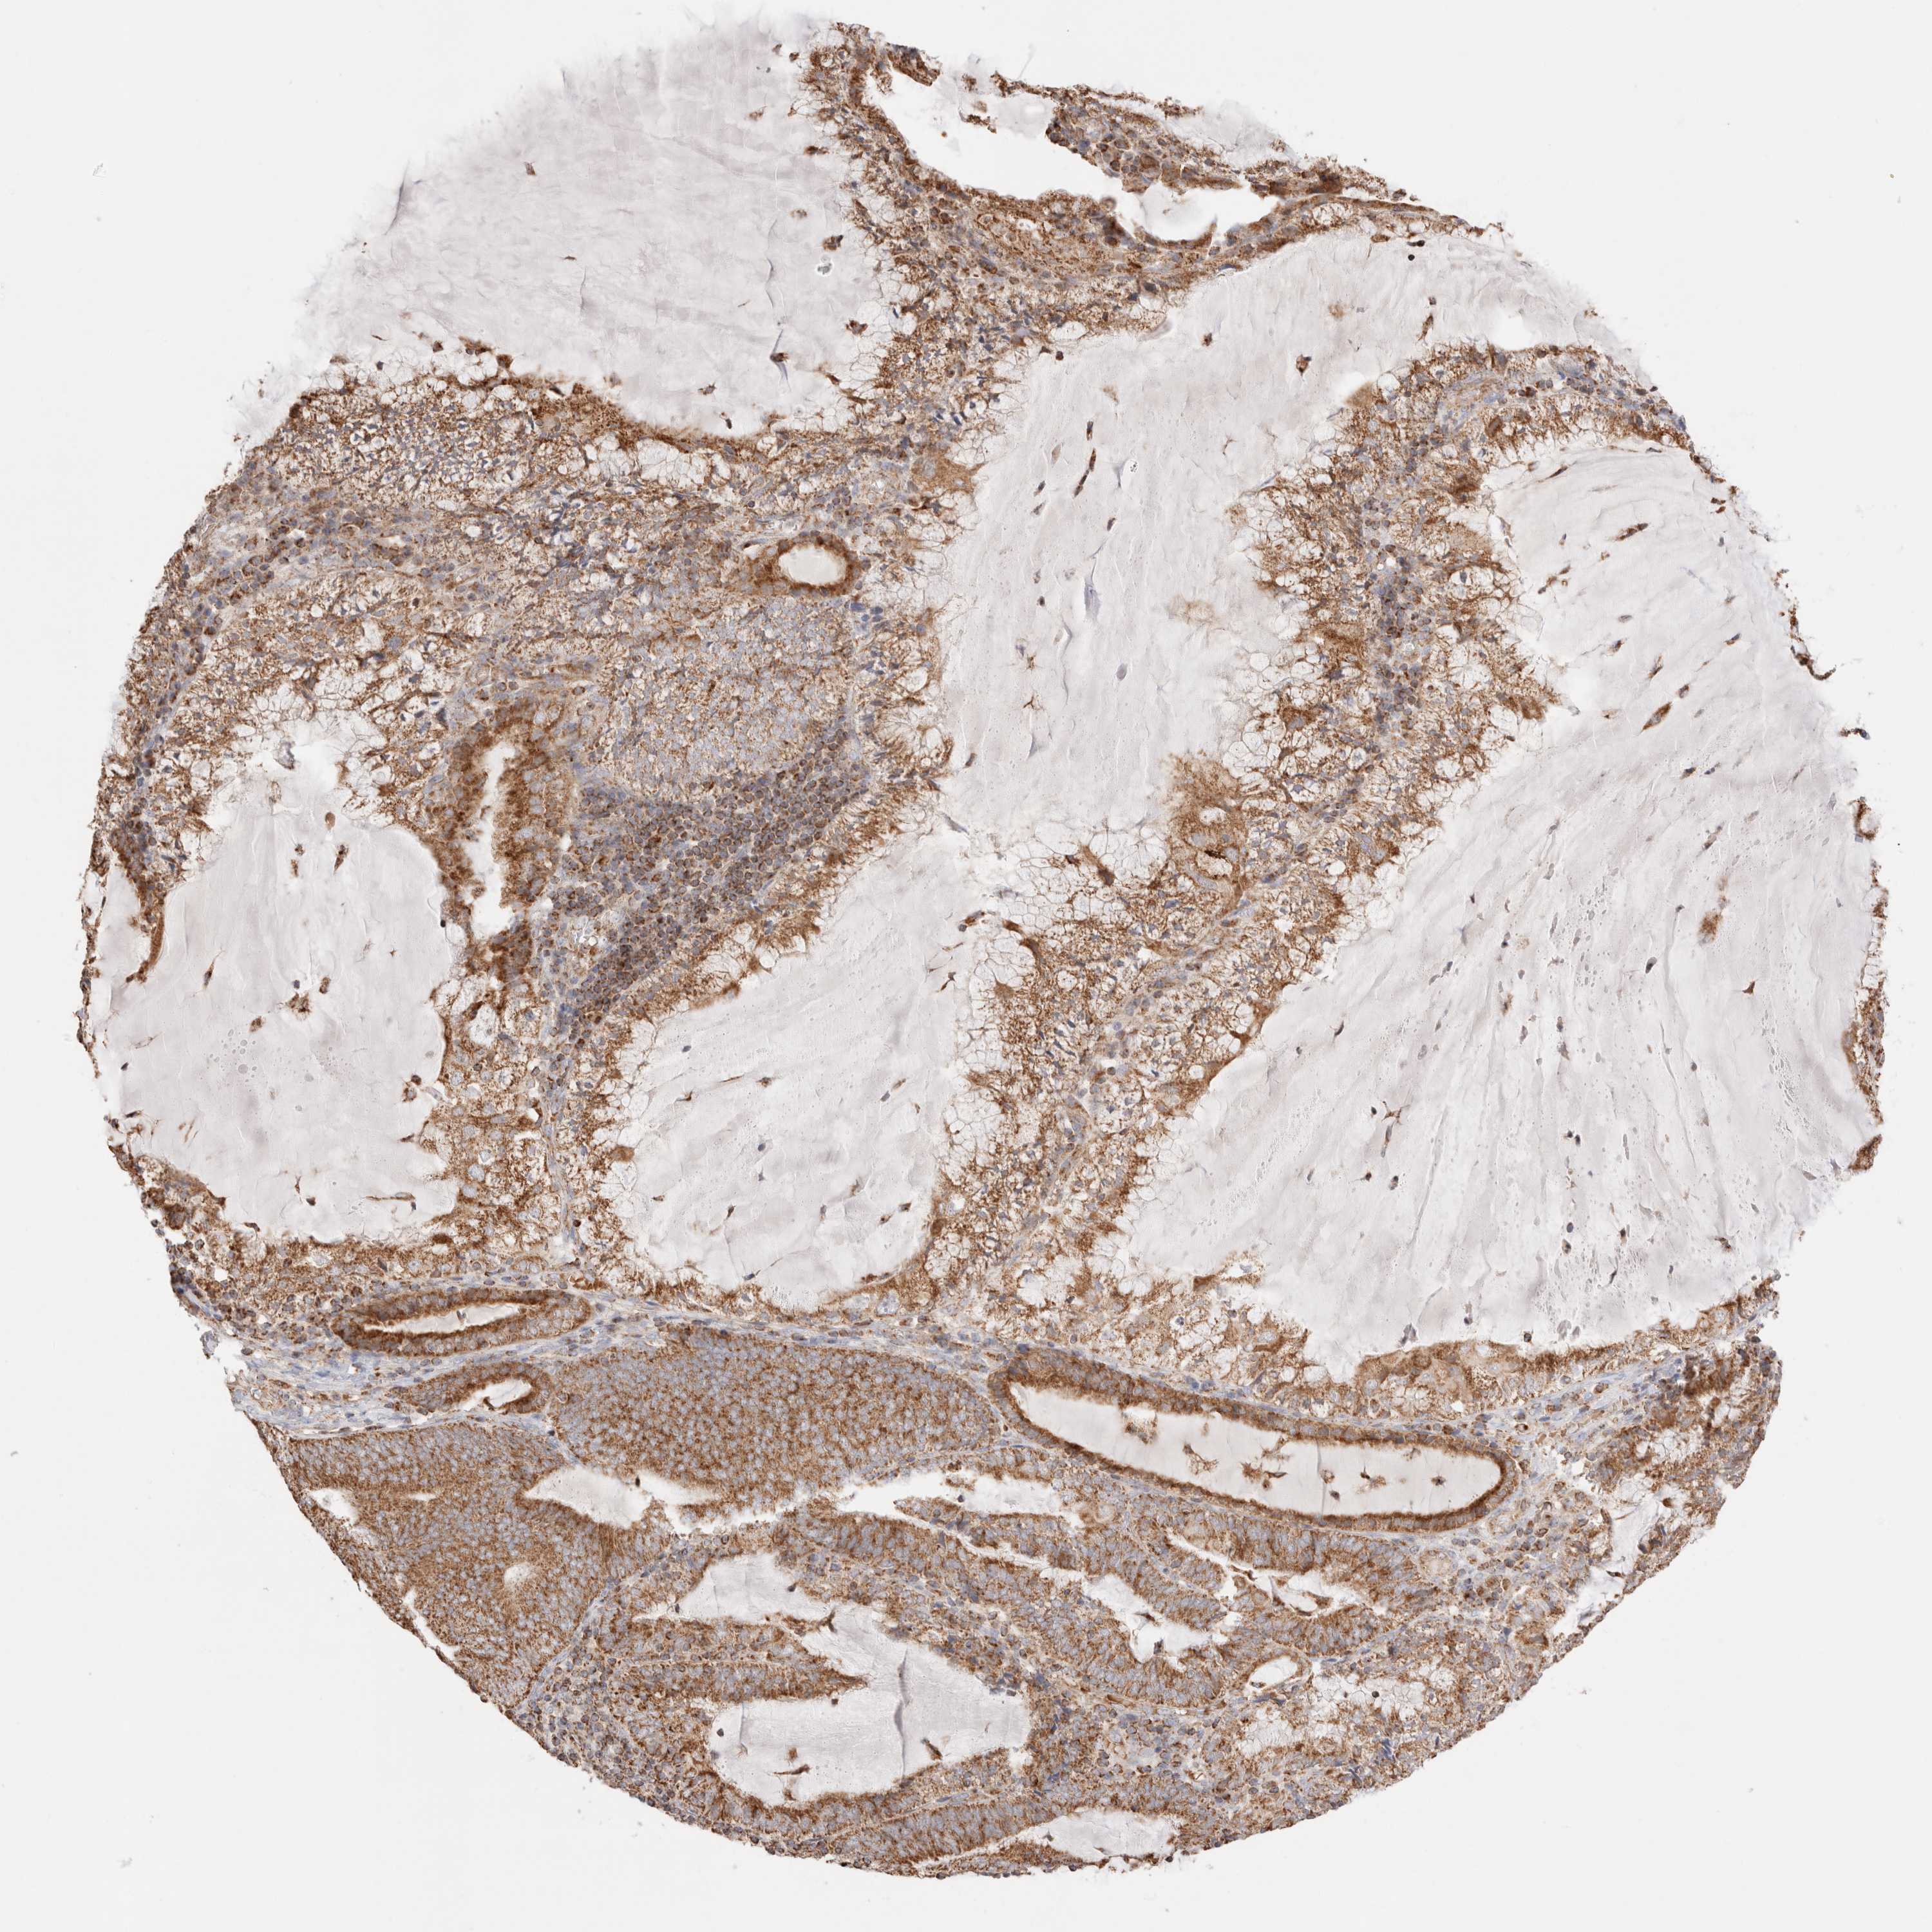

ENDOMETRIAL CANCER - Protein expressioni

A mouse-over function shows sample information and annotation data. Click on an image to view it in a full screen mode. Samples can be filtered based on level of antibody staining by selecting one or several of the following categories: high, medium, low and not detected. The assay and annotation is described here.

Note that samples used for immunohistochemistry by the Human Protein Atlas do not correspond to samples in the TCGA dataset.

Antibody stainingi

Antibody staining in the annotated cell types in the current human tissue is reported as not detected, low, medium, or high, based on conventional immunohistochemistry profiling in selected tissues. This score is based on the combination of the staining intensity and fraction of stained cells.

Each image is clickable and will lead to virtual microscopy that enables deeper exploration of all samples and also displays staining intensity scores, fraction scores and subcellular localization as well as patient and tissue information for each sample.

Antibody HPA027019

Staining

High

Medium

Low

Not detected

Intensity

Strong

Moderate

Weak

Negative

Quantity

>75%

75%-25%

<25%

None

Location

Nuclear

Cytoplasmic/membranous

Cytoplasmic/membranous,nuclear

Adenocarcinoma, NOS

Adenocarcinoma, metastatic, NOS